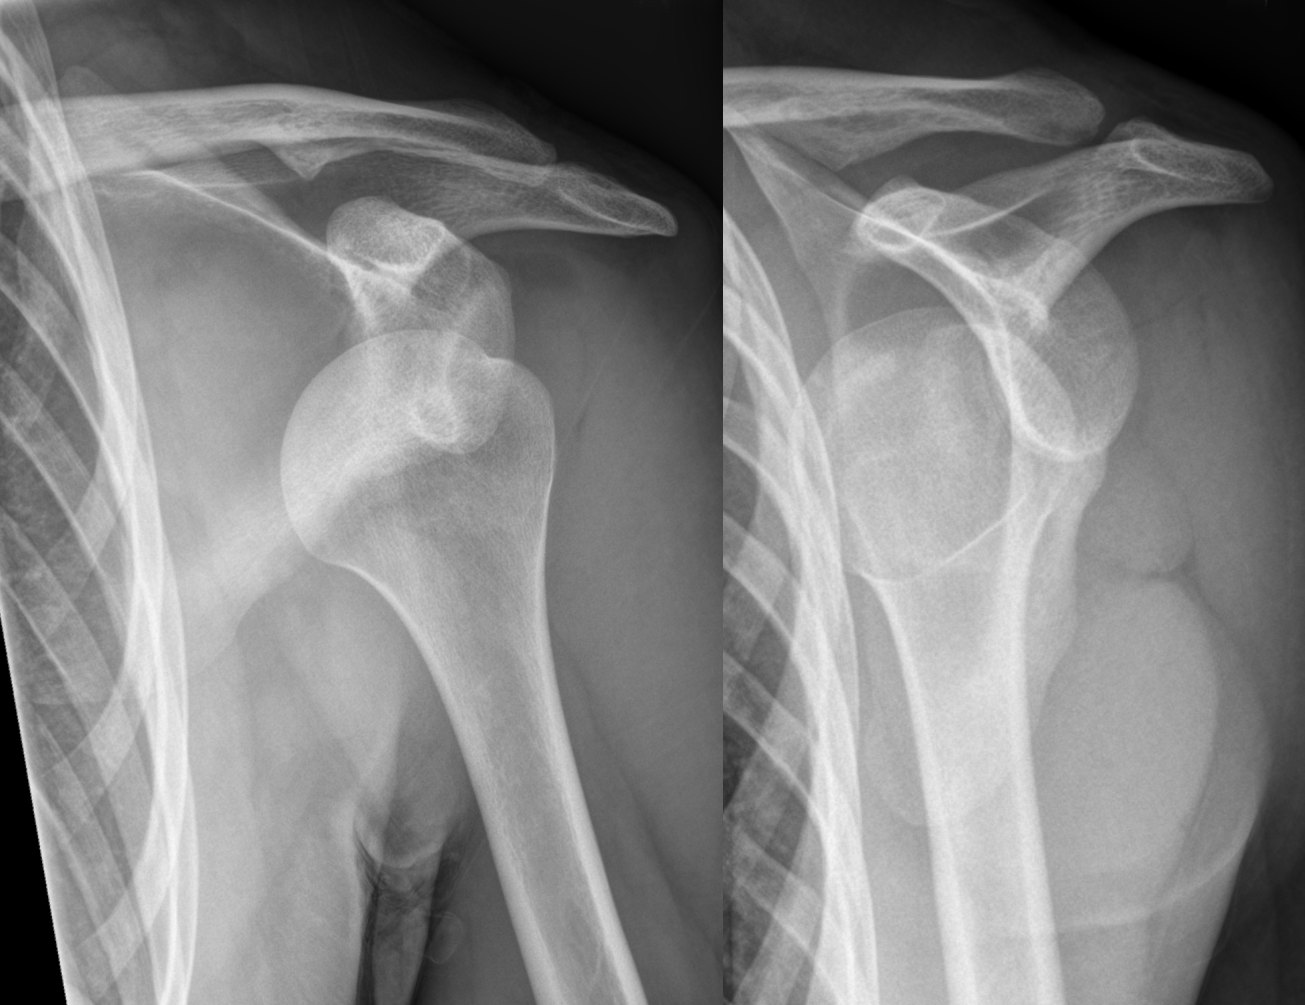

Shoulder has dynamic and static stabiliser to prevent dislocation. When a shoulder dislocates there is damage to the anterior labrum(static stabiliser).

Dislocation of the shoulder usually almost always recurs. Each episode of dislocation brings with it additional damage to the cartilage of the socket (Glenoid) and the ball (head of the humerus). This damage is not reversible